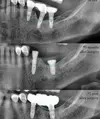

Periimplantitis

Peri-Implant Mucositis

Implant Treatment